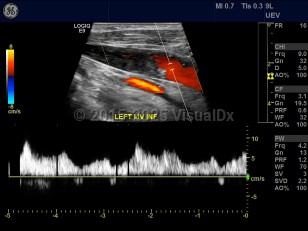

Internal jugular vein thrombosisInternal jugular vein thrombosis